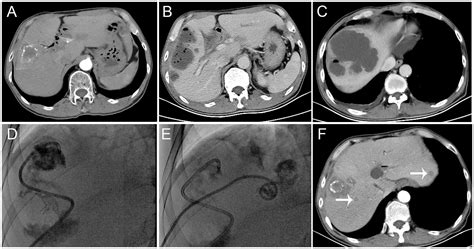

Diagnosing a liver abscess involves a combination of medical history, physical examination, and diagnostic tests. Imaging studies such as ultrasound, CT scans, and MRI are commonly used to visualize the abscess. Blood tests can help identify the underlying infection, and sometimes, a sample of the abscess fluid may be taken for culture and sensitivity testing.

The treatment of liver abscesses depends on the type and severity of the infection. For pyogenic abscesses, antibiotics are the primary treatment. The choice of antibiotic depends on the suspected or identified bacterial cause. In some cases, drainage of the abscess may be necessary, either through percutaneous drainage or surgical intervention.